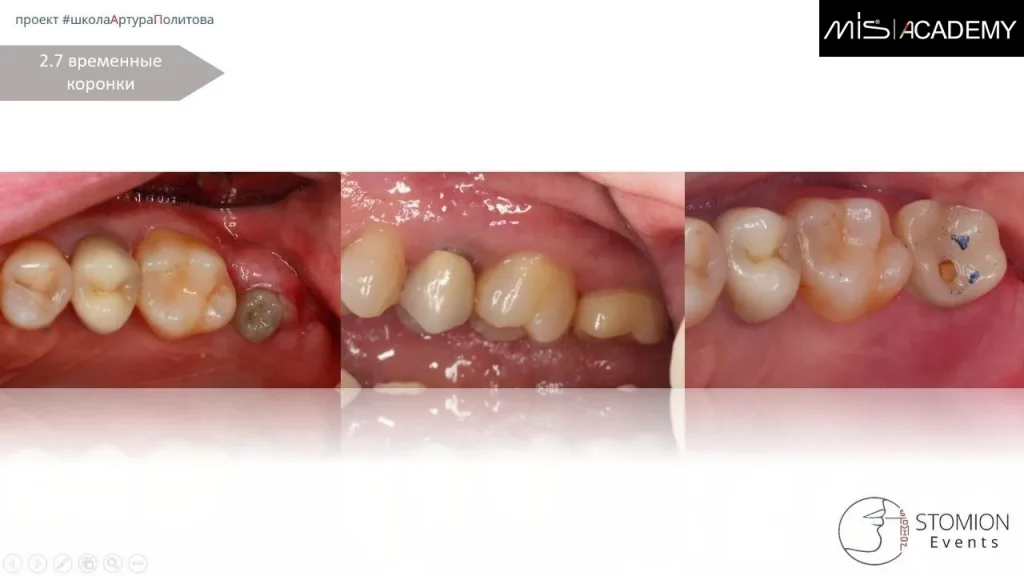

— Через 14 дней установка временной коронки.

— Через 3 месяца удаление 1.5, сгусток, колапол, ДСДТ вестибулярно, замена временной коронки 1.4 на коронку с консолью на 1.5.

— Через 12 дней снятие швов.

Параллельно установлен имплантат MIS C1 5×8 в позиции 2.7.

С уровня имплантата выполнена реставрация с цементной фиксацией на индивидуальном абатменте.